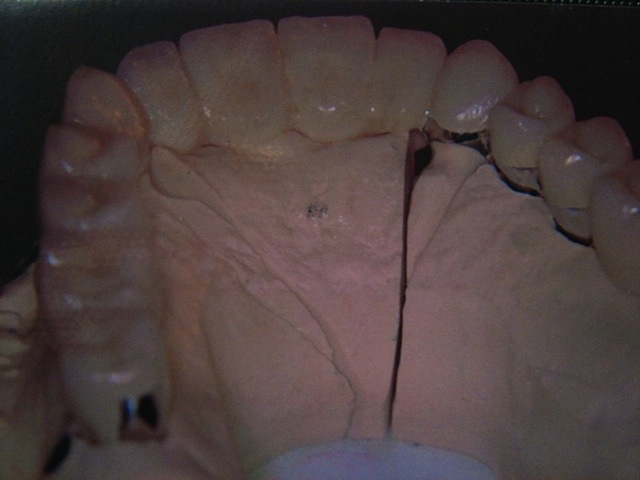

Die folgenden Patientenfälle sollen Ihnen einen Einblick in die Möglichkeiten der modernen Implantation geben.

Implantation – Patientenbeispiel 2: